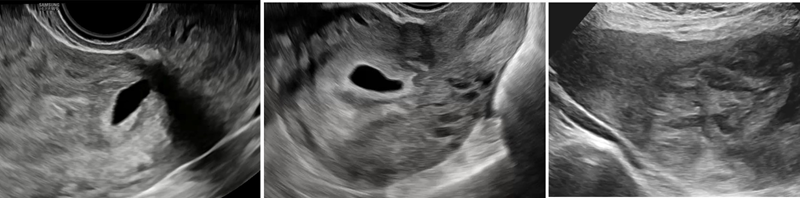

Dấu hiệu thai bám sẹo trên siêu âm

Ở giai đoạn sớm của quý I (6-9 tuần) có 2 dấu hiệu điển hình, bao gồm:

- Thai bám sẹo - marker sớm của NCRL: Trên siêu âm, đặc trưng bởi túi thai (có hoặc không kèm tổ chức nhau) làm tổ tại vị trí sẹo mổ cũ, trong khi buồng tử cung và kênh cổ tử cung trống. Túi thai thường có hình tam giác ở giai đoạn <8 tuần, chuyển dạng bầu dục khi >8 tuần và có thể lấp đầy khuyết sẹo. Lớp cơ tử cung giữa túi thai và bàng quang mỏng hoặc mất, kèm tăng sinh mạch quanh túi thai trên Doppler. Bên trong túi thai có thể ghi nhận yolksac, phôi và hoạt động tim thai tùy giai đoạn. Dựa vào hướng phát triển của túi thai, phân loại theo đồng thuận Delphi gồm: type 1 (túi thai phát triển chủ yếu về phía buồng tử cung), type 2 (túi thai nằm chủ yếu trong vùng sẹo), và type 3 (túi thai phát triển ra ngoài thanh mạc), phản ánh mức độ xâm lấn và nguy cơ tiến triển của bệnh lý. Theo diễn tiến thai kỳ, do hiện tượng “di chuyển” tương đối của bánh nhau, sau khoảng 9 tuần, túi thai có thể không còn biểu hiện bám thấp rõ ràng, tuy nhiên, bánh nhau vẫn khu trú tại vị trí khuyết sẹo (Placenta in the niche). Ngoài ra, hình ảnh thai bám thấp gần lỗ trong cổ tử cung cũng là dấu hiệu cần được theo dõi và đánh giá thận trọng.

- Thai bám thấp: Túi thai làm tổ gần lỗ trong cổ tử cung.

.png)

Dấu hiệu túi thai thấp